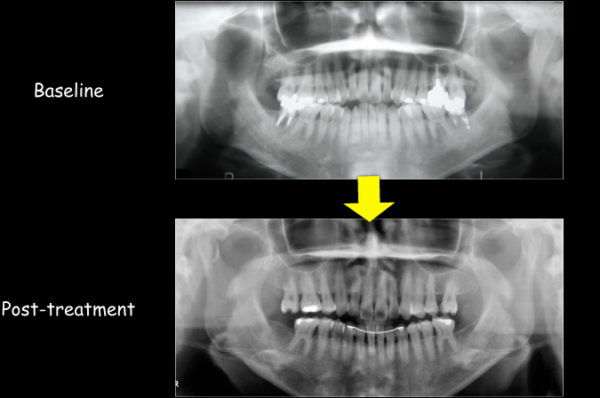

黄色で〇をつけた歯は、すでに神経の無い「失活歯」です。

治療前後のレントゲン写真を見ると、失活歯(根っこにお薬が入っている歯)が減っているのがわかります。

20年もの長い間、ほぼ歯の治療を行わず済んだのは、第一にこの患者さまがしっかりとお手入れとメンテナンスを欠かさず、努力された事に他なりません。

それに加えて、この矯正治療によって、状態の良い歯のみで歯列を作り、歯並びと咬み合わせを改善できたことも、一つの要因であったと思います。